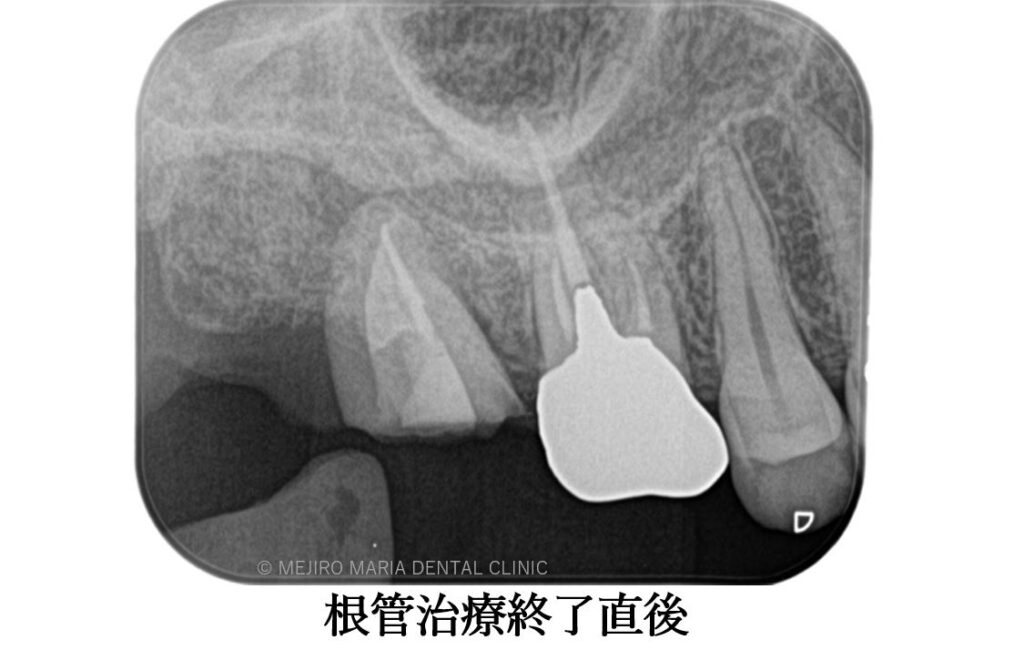

左上の親知らずを抜歯後、すぐに右上7番部位に移植を施し2週間経過後に精密根管治療を行いました。

精密根管治療終了後3ヶ月で、術前に確認できた病変の縮小は顕著に確認でき、予後経過は良好と判断します。今後、最終補綴処置に移行し経過観察を行っていきます。

手術後、2週間で移植歯の生着を確認し、通法通りの精密根管治療を施したことで、根尖周囲組織に確認できた病変も3ヶ月後の経過観察では縮小を確認しました。

歯牙移植を行った場合、移植歯の歯髄組織は血流を失うため、歯牙生着を確認後に精度の高い根管治療と定期的な経過観察を行うことが必要になります。